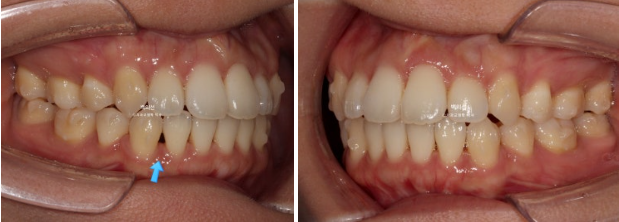

25.07

중심선은 일치하고

어금니 교합은 1급이고 물샐틈 없습니다.

23.01~25.07

유지장치까지 들어간 모습입니다.

이제 전 후 비교해보겠습니다.

총 치료기간은 2년 6개월, 재제작은 총 2회 했습니다.